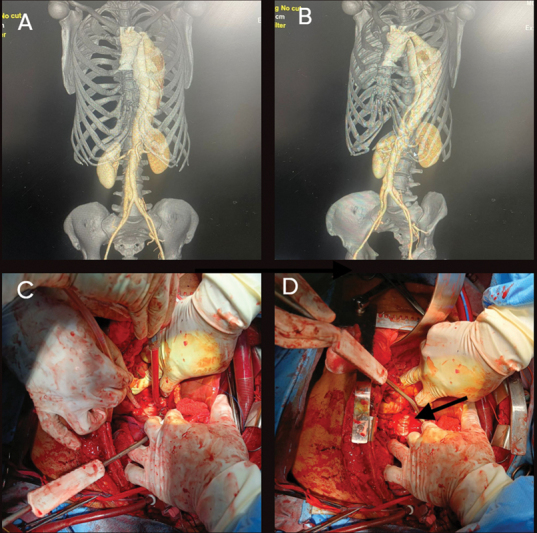

冷冻象鼻(FET)一直是治疗急性和慢性主动脉夹层的主要方法。尽管文献中报道了各种并发症,但据我们所知,血管内移植物导致胸降主动脉破裂的报道尚未发表。我们报告在先前的A型主动脉夹层导致胸降主动脉破裂的保留瓣根置换术后进行FET手术。

The frozen elephant trunk (FET) has been a mainstay in the treatment of acute as well as chronic aortic dissections. Although various complications have been reported in the literature, rupture of the descending thoracic aorta by the endovascular graft has, to our knowledge, not been published. We report an FET procedure following previous valve-sparing root replacement for Type A aortic dissection leading to rupture of the descending thoracic aorta.